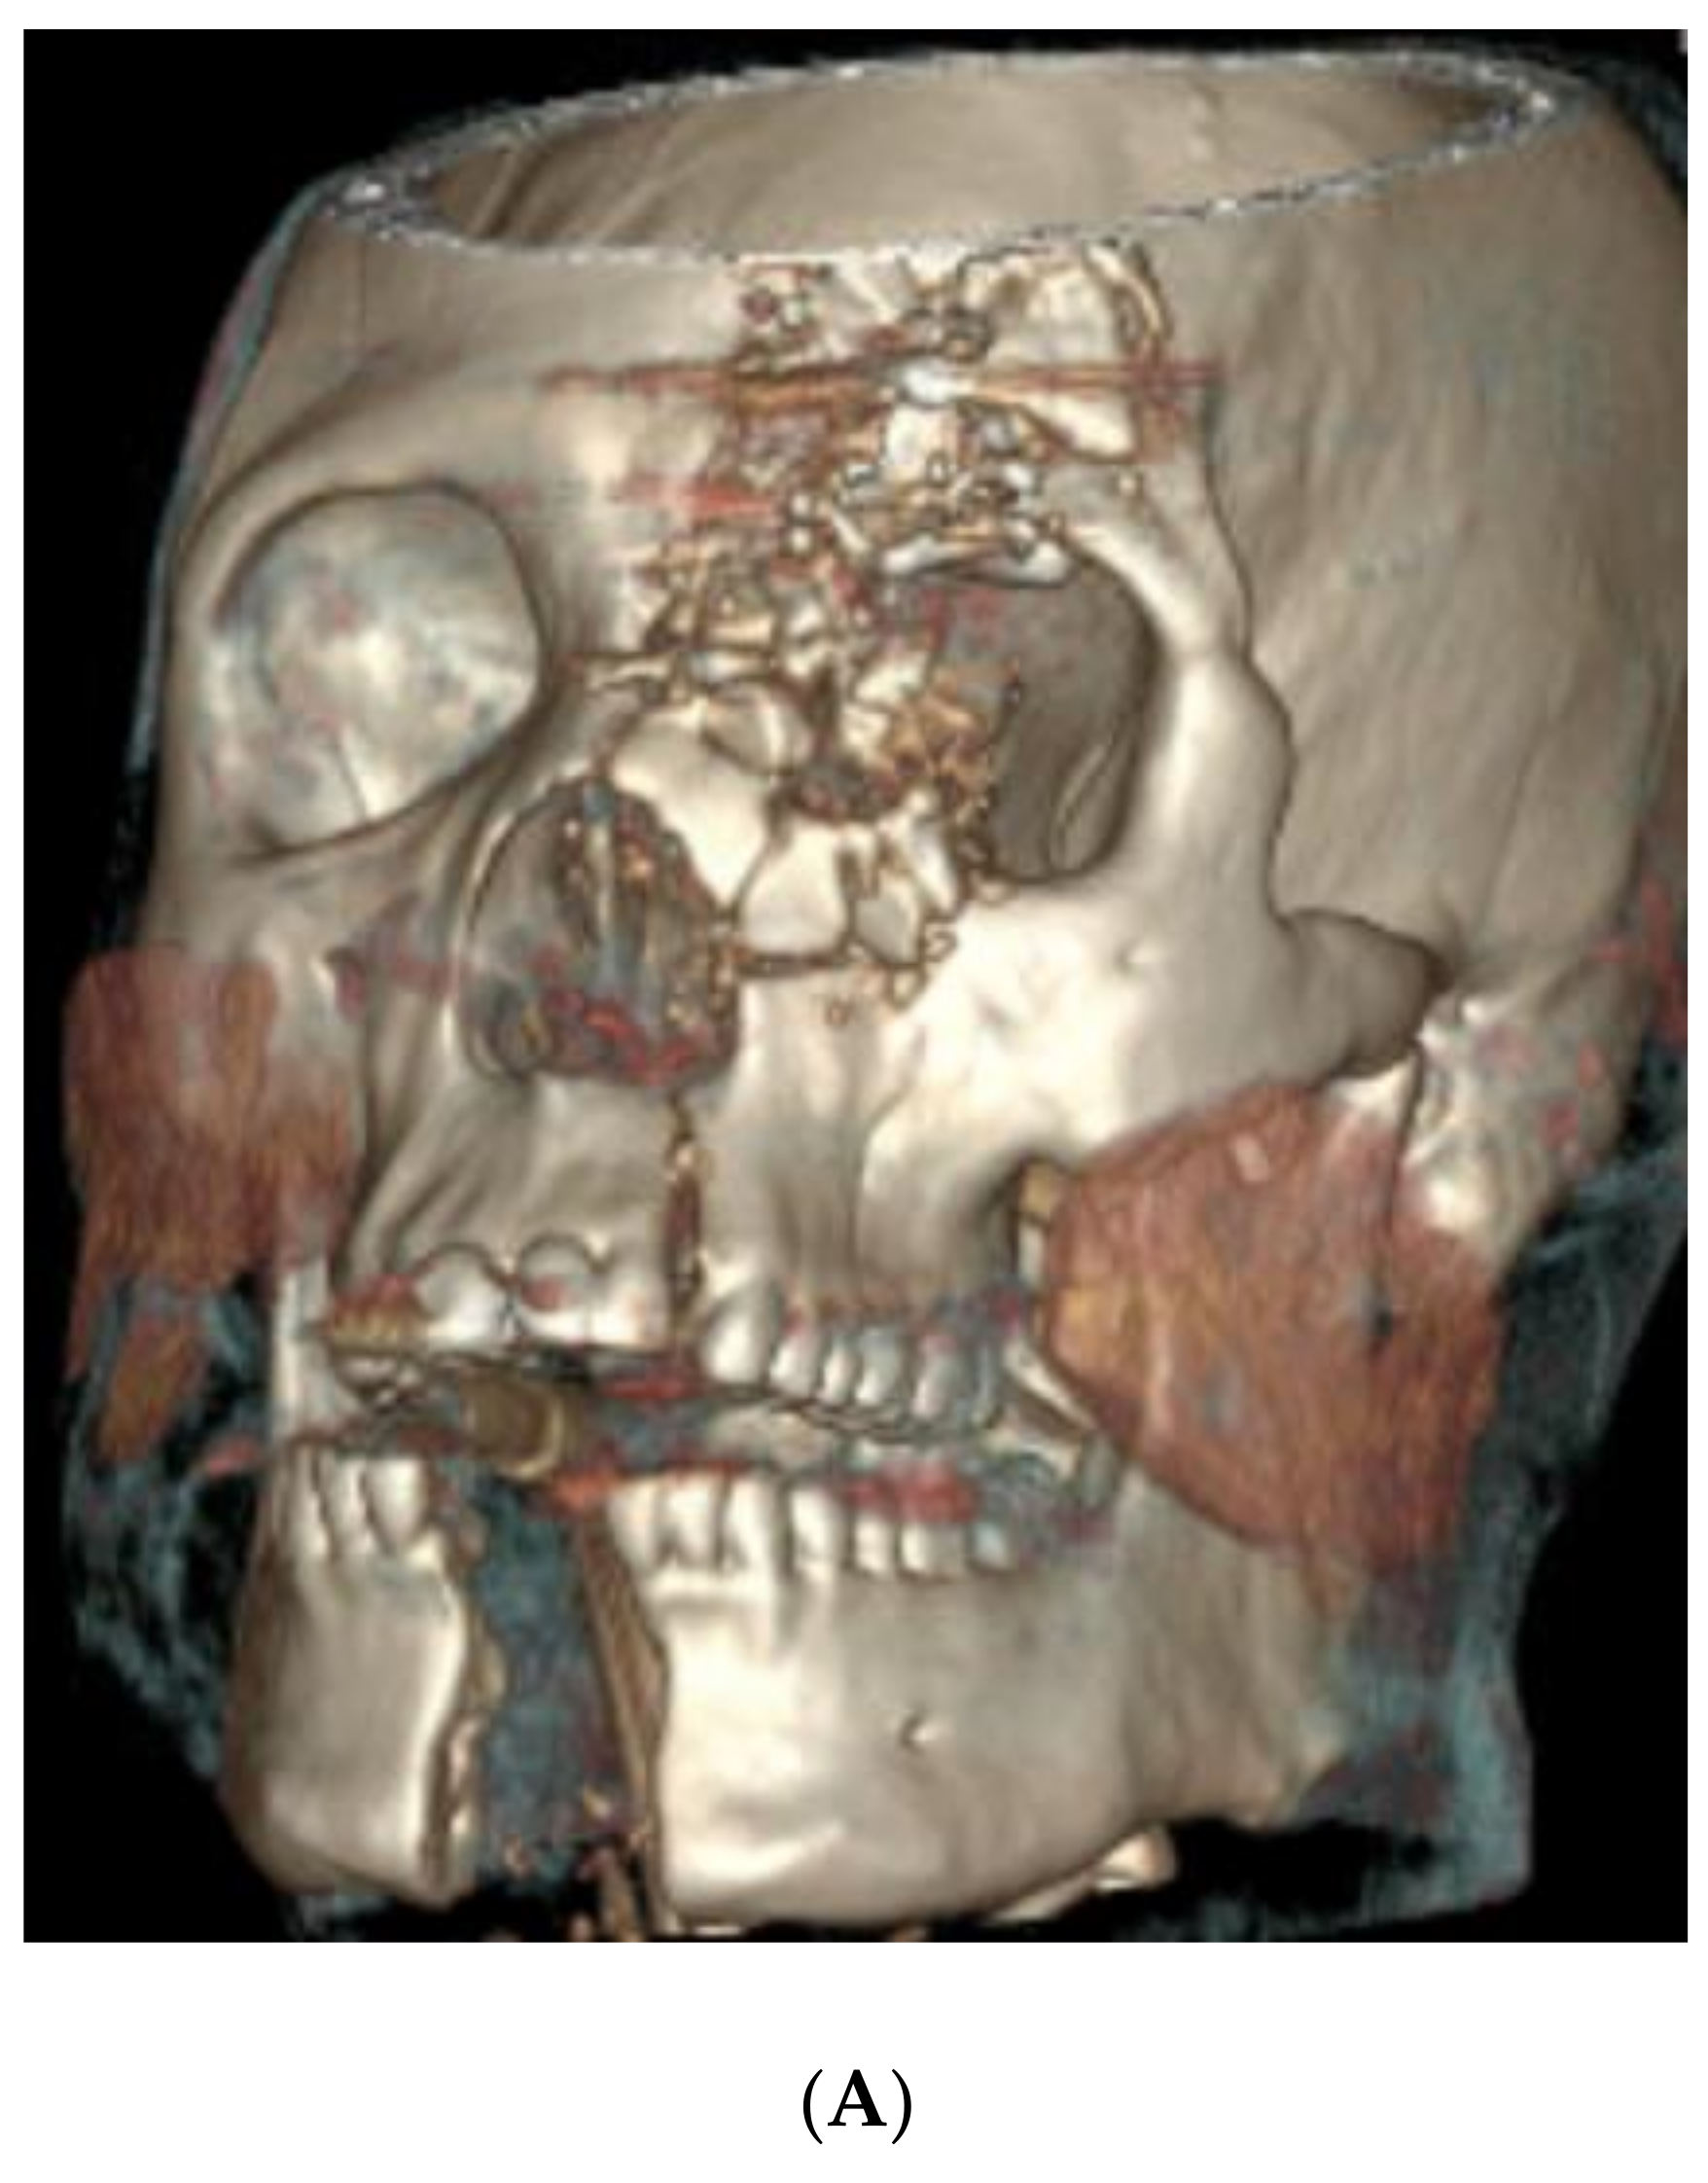

4.1. Case 1 (Occlusal Splint)

- An extensive calvarial fracture involving the left frontal sinus and left cribriform plate;

- Comminuted fractures of the left medial, superior, and inferior orbital walls;

- Left Le Fort I/II maxillary fractures;

- A comminuted transverse palatal fracture;

- A left mandibular symphyseal fracture (with 2.4 cm diastasis between the fracture segments);

- A comminuted nasal bone fracture.